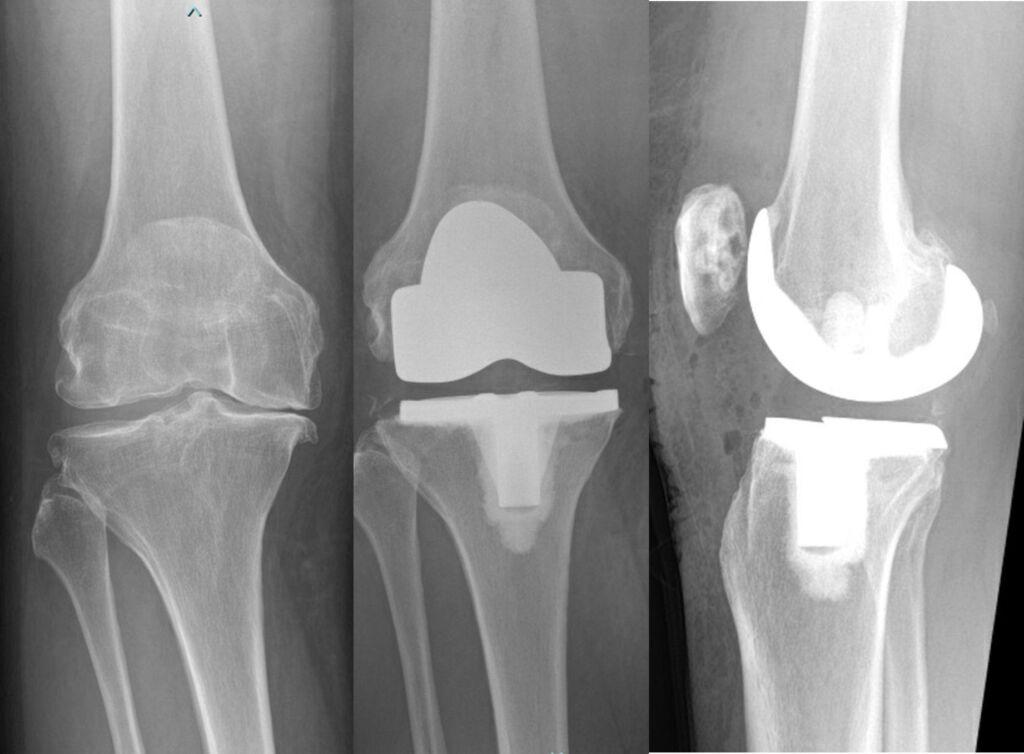

JOINT REPLACEMENT / ARTHOPLASTY

Advanced knee arthritis – left image,

Total knee replacement – right image